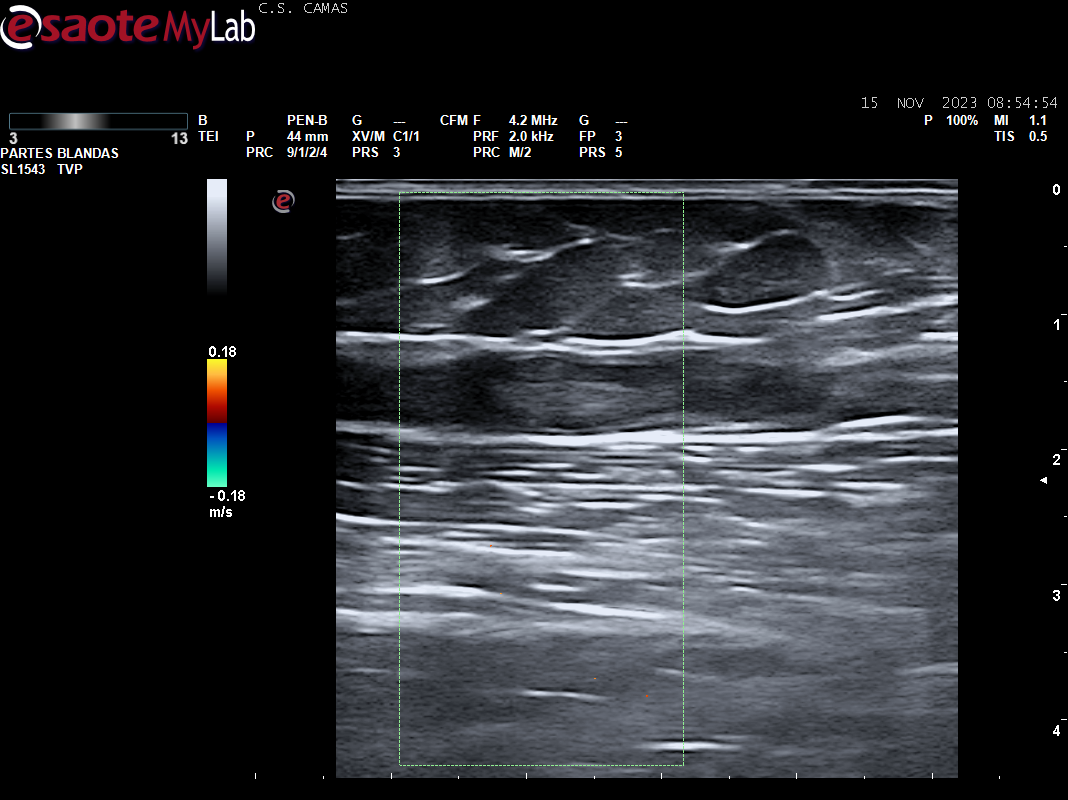

A la exploración se aprecia cordón varicoso en cara interna del muslo izq. Se realiza POCUS en consulta para descartar la presencia de TVP.

Ecografia vascular cara interna del muslo izq: Trombosis de todo el recorrido de la safena izq con dolor al paso de la sonda por colaterales inferiores que colapsan. Presenta además en zona del cayado de la safena imagen heterogenea sin apreciar la llegada de la safena a la femoral común compatible con arrancamiento de la misma.

Trombosis de todo el recorrido de la safena interna izquierda con tromboflebitis de las colaterales inferiores que concuerda con el diagnóstico hospitalario.